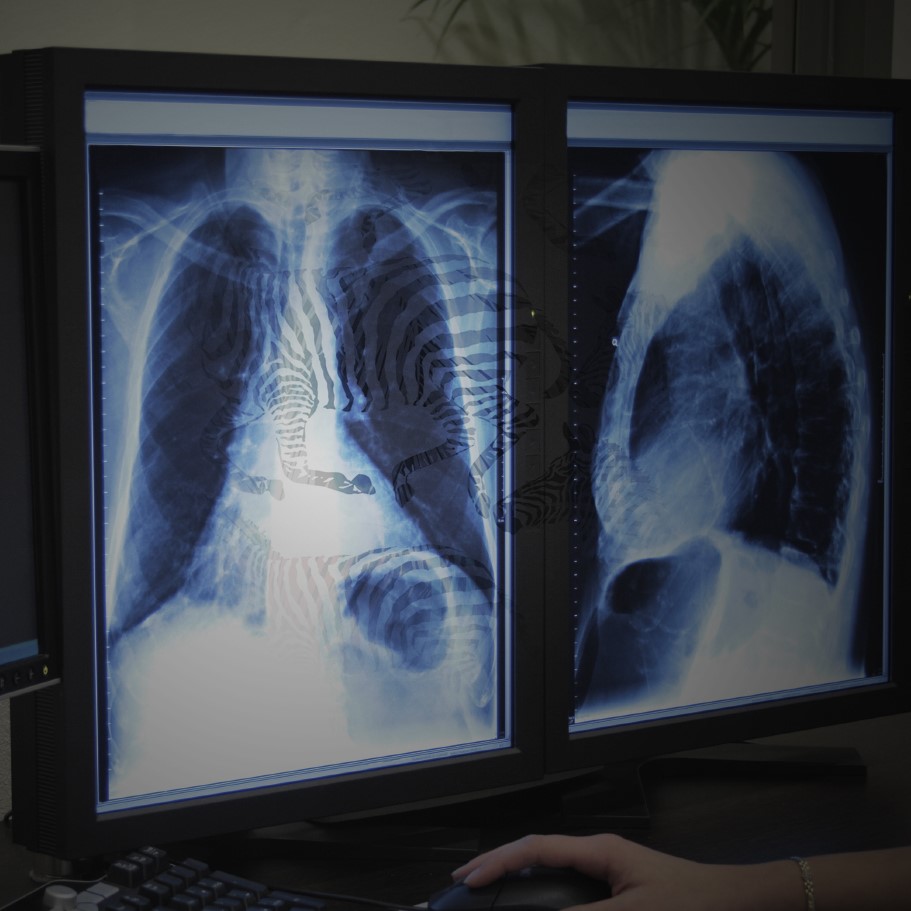

I suppose for most physicians, we write to process a tough interaction, a disheartening conversation, or a terrible day. In truth, I write daily. And most often, it’s to process someone else’s terrible day. That’s the job of a radiologist. To look at a patient’s CT scan or ultrasound or MRI or x-ray, interpret what I see, and write a report. To put in writing that there is a new cancer, or the tumor hasn’t responded to treatment, or the appendix is ruptured.

But radiology reports can be tiresome, for reasons existential as well as aesthetic. By convention, a radiology report is a neatly divided combination of fact and opinion. In the first portion, the “Findings,” I describe the facts that I see on the screen, and in the second section, the “Impression”, I offer my professional opinion of what these facts mean. But if you were to read my report, you might not tell one section from the other. This is largely because convention also dictates that, in radiology reports, we write in the passive voice. The convention has been passed down from radiology attending to resident since the beginning, and the result is a semblance that the radiologist’s impressions represent the objective truth. No liver mass is seen. Seen by whom? By me?

Instead, I usually write something unimaginative—Liver: Normal—or, worse, noncommittal and vague. Tiny density in the liver is too small to characterize but statistically, is likely a benign cyst. Please correlate clinically for history of malignancy. Because everything exists, on the radiologist’s monitor, in uncertain shades of grey.